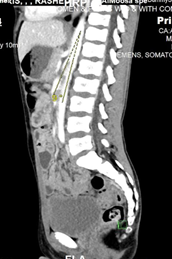

Fig 3: Axial image of IV contrast enhanced CT scan of the abdomen demonstrates duodenal dilatation with transitional zone at the aortomesenteric window.

Fig 4: Sagittal image of IV contrast enhanced CT scan of the abdomen demonstrates aortomesenteric sharp angle ( 9°) (Normal range > 22°).

The tight and sharp aortomesenteric distance and angle respectively along with the gastric and duodenal dilatation are in favour of superior mesenteric artery syndrome.

Figure 3

Figure 4